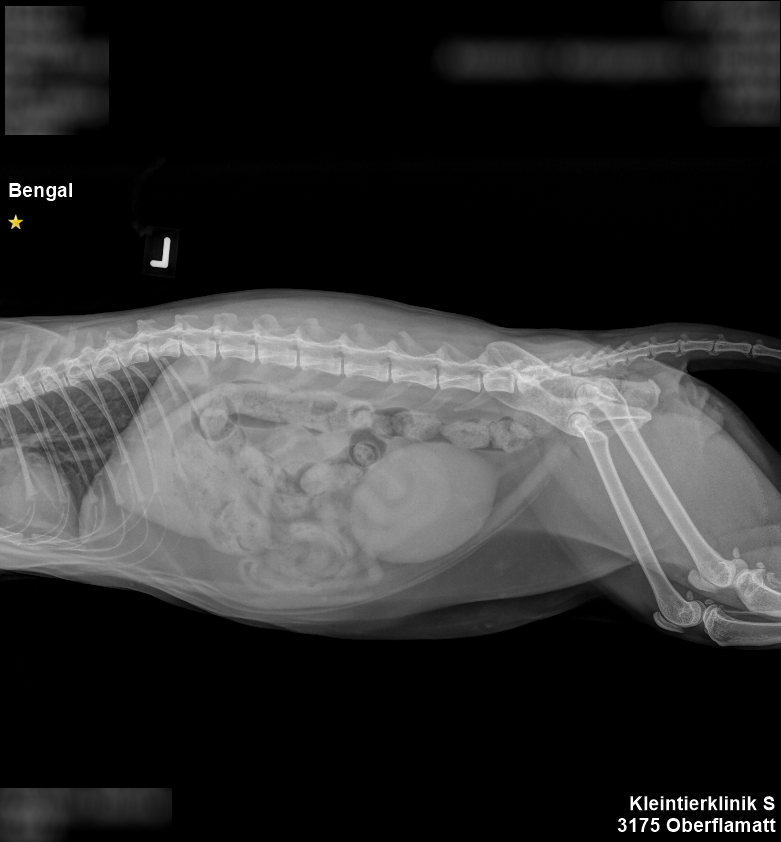

Die ersten Röntgenbilder zeigten schwere Quetschungen im Beckenbereich, weitere Untersuchungen brachten eine Leberblutung und eine Verletzung einiger Schwanzwirbel an den Tag.

Ausserdem war das Kreuzband am linken Hinterlauf gerissen. Und schliesslich landete auch noch ein Blasenstau auf der langen Verletzungsliste. Chantal Imboden dazu: „Seit er drei Monate alt ist, begleitet uns Simba durchs Leben. Ihn dann so zu sehen, tat uns unendlich leid. Aber nachdem er stabilisiert und zwei Tage später operiert werden konnte, schöpften wir neuen Mut.“

Indes, der stolze Kater musste einiges über sich ergehen lassen: Die Wirbelverletzung war so schwer, dass der Schwanz amputiert werden musste, und das gerissene Kreuzband wurde mit einer Titan-Version ersetzt. Besonders gravierend war jedoch die Tatsache, dass Simba die beiden Hinterbeine nicht bewegen konnte; die Auswirkung der heftigen Quetschungen.